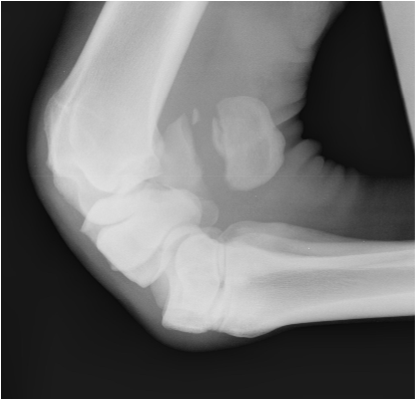

• What is the correct term for this radiographic view?

flexed lateromedial